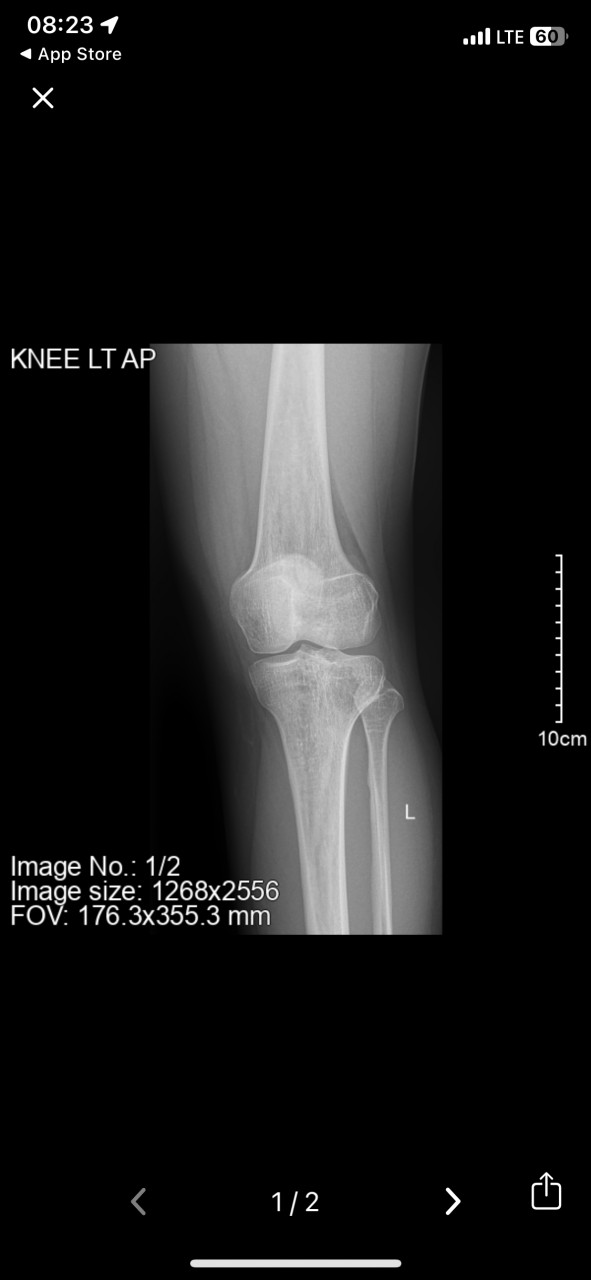

Заключение Очаговое структурное изменение наружного мыщелка левой большеберцовой кости.

Здравствуйте. На рентгене видно очаговое изменение в наружном мыщелке большеберцовой кости  это может быть следствием нагрузки, травмы или дегенеративного процесса. Наличие или отсутствие отёка по снимку не определить т.к отёк оценивается при осмотре, пальпации или с помощью УЗИ,МРТ.

Если есть отёк и боль, временно можно применять нестероидные противовоспалительные мази (например Диклофенак, Фастум-гель), но лучше уточнить диагноз очно при осмотре.